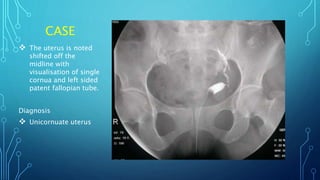

CASE

 The uterus is noted

shifted off the

midline with

visualisation of single

cornua and left sided

patent fallopian tube.

Diagnosis

 Unicornuate uterus

CASE  The uterusis noted shifted off the midline with visualisation of single cornua and left sided patent fallopian tube. Diagnosis  Unicornuate uterus